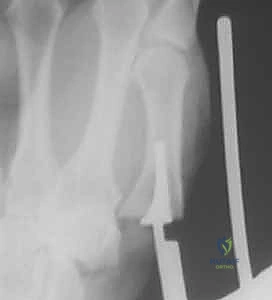

2. التصوير الإشعاعي وتصنيف إيتون-ليتلر (Eaton-Littler Classification)

تُعد الأشعة السينية (X-rays) أداة ضرورية لتأكيد التشخيص وتقييم مدى الضرر. يستخدم الدكتور هطيف تصنيف "إيتون-ليتلر" العالمي لتحديد مرحلة المرض، والذي يبني عليه قرار التدخل الجراحي:

* المرحلة الأولى (Stage I): اتساع طفيف في مساحة المفصل (دليل على التهاب الغشاء الزلالي وتراخي الأربطة)، الغضروف لا يزال سليماً، ولا توجد نتوءات عظمية.

* المرحلة الثانية (Stage II): تضيق بسيط في مساحة المفصل (بداية تآكل الغضروف)، مع ظهور نتوءات عظمية صغيرة (أقل من 2 ملم)، وبداية انزلاق المفصل.

* المرحلة الثالثة (Stage III): تضيق شديد أو انعدام لمساحة المفصل (احتكاك عظم بعظم)، نتوءات عظمية كبيرة (أكبر من 2 ملم)، انزلاق واضح للمفصل، وتصلب العظام تحت الغضروف.

* المرحلة الرابعة (Stage IV): دمار كامل للمفصل القاعدي (CMC joint) ويمتد التلف ليشمل المفصل المجاور بين العظم المربعي والعظم القاربي (Scaphotrapezial joint).